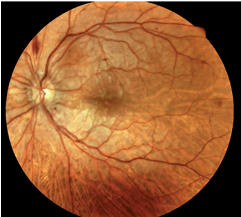

Purtscher-like Retinopathy an Unusual Complication of Retrobulbar Anesthesia after Cataract Surgery

Parinya Srihatrai, Hataiphat Tamnakpo

47-52